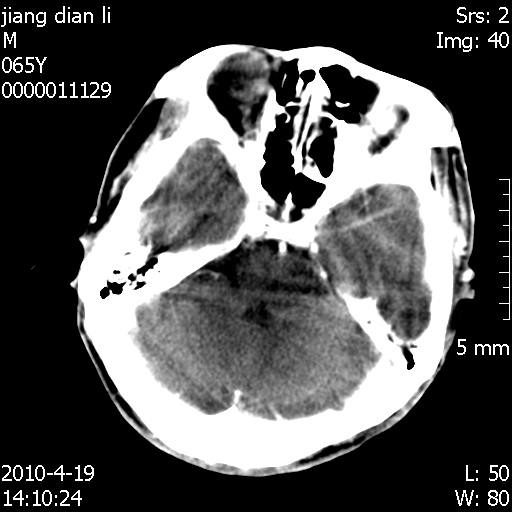

老年男性,突发左下肢无力1天,其余有价值的检查都没有。平扫ct值大约60hu,增强后ct值没什么改变,请大家讨论一下这个病例是什么?说明诊断理由。

左小脑、右大脑顶叶多发圆形高密度病灶,其周环状低密度影。考虑多发脑出血。隔期观察。

至于是出血还是微小钙化所致的高密度无法考证,三个都出血也不是一点都不可能,同一种组织学类型的肿瘤受到同一个外来的因素影响后会表现出相同的病理变化。说实在的,我本身支持转移瘤的,就是想不通为什么不强化?我认为单纯脑出血的边缘不会那么光滑,并且那也不是出血的常见部位,多发也不常见。

刚刚复习了转移瘤的不典型ct征象,有4条,分享给大家:

1、高密度灶:多为瘤内有较多沙粒体钙化所致,而不是出血,ct值可高达95hu;

2、无强化;

3、无水肿;

4、无占位效应。